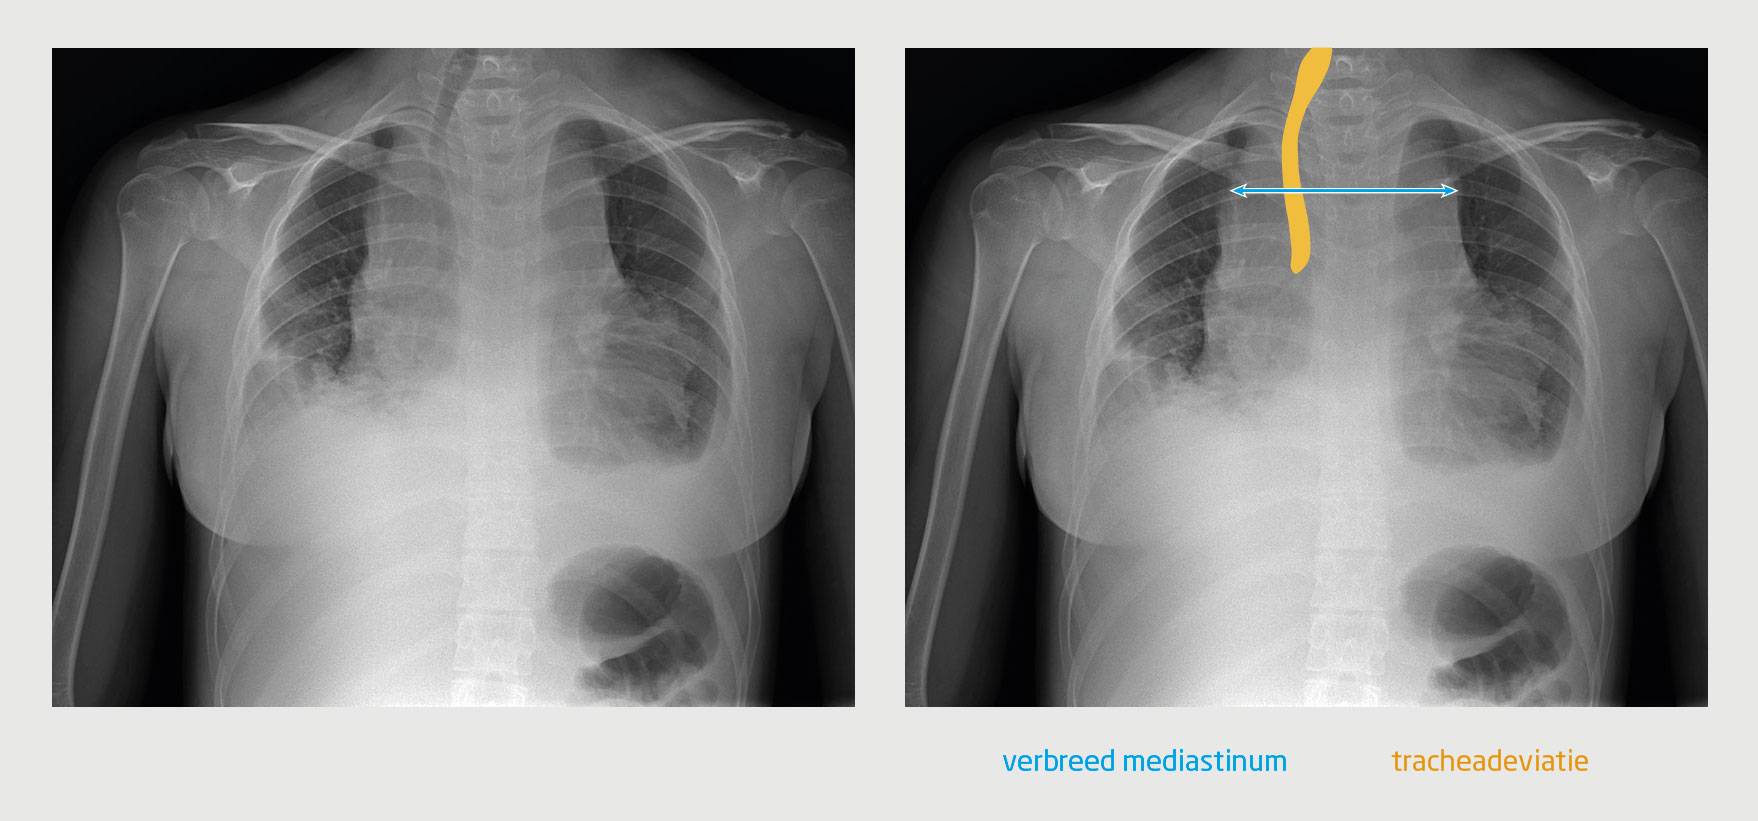

Figuur 2

Compartimenten van het mediastinum

Figuur 2 | Compartimenten van het mediastinum

Het mediastinum bestaat uit 3 compartimenten. Het voorste mediastinum bevat de thymus, lymfklieren, vet en de V. brachiocephalica sinistra (roze). Het middelste mediastinum bevat de trachea, de carina, de oesophagus, lymfeklieren, de grote vaten en het hart (blauw). Het achterste mediastinum bevat de thoracale wervelkolom en paravertebrale weke delen (geel).1

Het mediastinum bestaat uit 3 compartimenten (figuur 2).1 Het voorste mediastinum bevat de thymus, lymfklieren, vet en de V. brachiocephalica sinistra. Het middelste mediastinum bevat de trachea, de carina, de oesophagus, lymfeklieren, de grote vaten en het hart. Het achterste mediastinum bevat de thoracale wervelkolom en paravertebrale weke delen. Bij kinderen is de oorzaak van een verbreed mediastinum meestal gelegen in het voorste mediastinum. Vaak gaat het om een maligniteit. Een uitgebreid overzicht van de oorzaken van een verbreed mediastinum bij kinderen staat in de tabel.